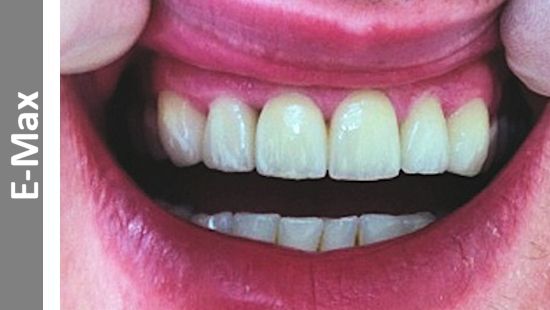

Sky Dental Ceramics is a professional service creating dental restorations that have a truly natural look.

Our reputation and service is based on over 25 years of knowledge, skills and experience.